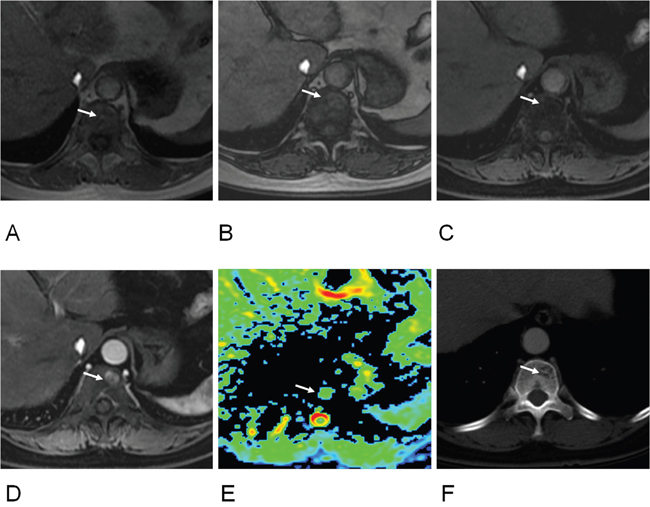

Figure 2: 60-year old women with atypical hemangioma of T11 vertebra. (A) T1-weighted image showed an isointense signal lesion on T11 vertebra (arrow); (B) Out-phase image showed a hyperintense signal lesion (arrow), ratio of SI loss between in- and out-phase was 0.35; (C) Fat suppressed (FS) T1-weighted images showed an isointense signal (arrow), ratio of SI loss between T1 and FS T1 was 0.74; (D) Early enhanced image showed hyperintense signal (arrow) (enhancement ratio, 4.47; SIR, 2.21); (E) Apparent diffuse coefficient (ADC) was 1.13 x10-3 mm2/s (arrow). (F) CT image revealed a hypo-dense lesion with internal striated appearance matching with hemangioma (arrow).

Figure 3: 63-year old women of hepatocellular cell carcinoma with metastasis of T9 vertebra. (A) T1-weighted image showed a hypointense signal lesion on T9 vertebra (arrow); (B) Out-phase image showed hyperintense signal (arrow), ratio of SI loss between in- and out-phase was 0.01; (C) FS T1-weighted images showed hyperintense signal (arrow), ratio of SI loss between T1 and FS T1 was 0.16; (D) Early enhanced image showed hyperintensity (arrow) (enhancement ratio, 0.90; SIR, 4.26); (E) DW image showed hyperintensity at b value of 1500 s/mm2 (arrow); (F) Apparent diffuse coefficient (ADC) was 0.61 x10-3 mm2/s (arrow).